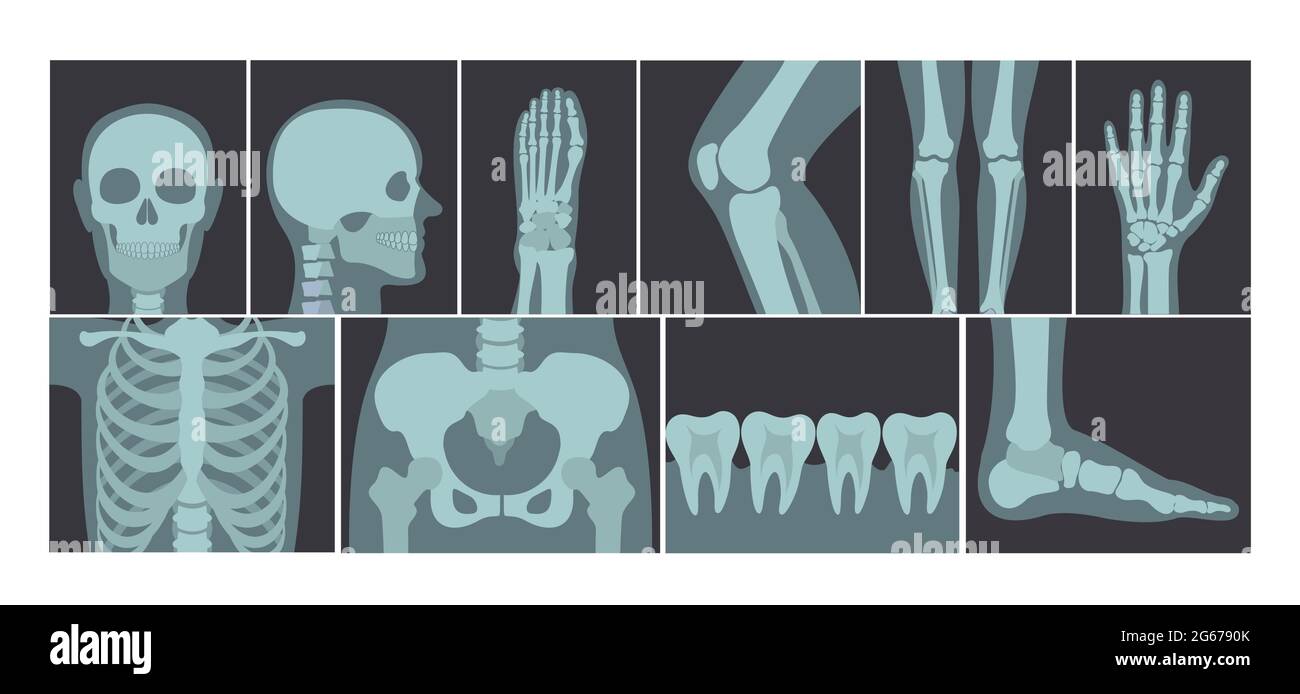

RF2G6790K–Ensemble d'illustrations vectorielles de nombreux clichés de rayons X du corps humain, images radiographiques de la tête, des mains, des jambes et d'autres parties du corps sur fond blanc.